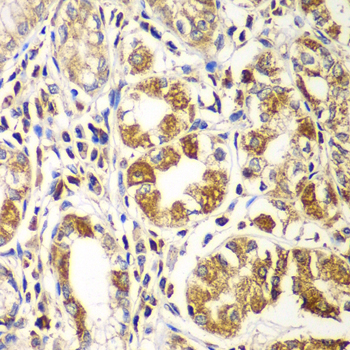

Immunohistochemistry of paraffin-embedded human gastric using RAC1 at dilution of 1:100 (40x lens).